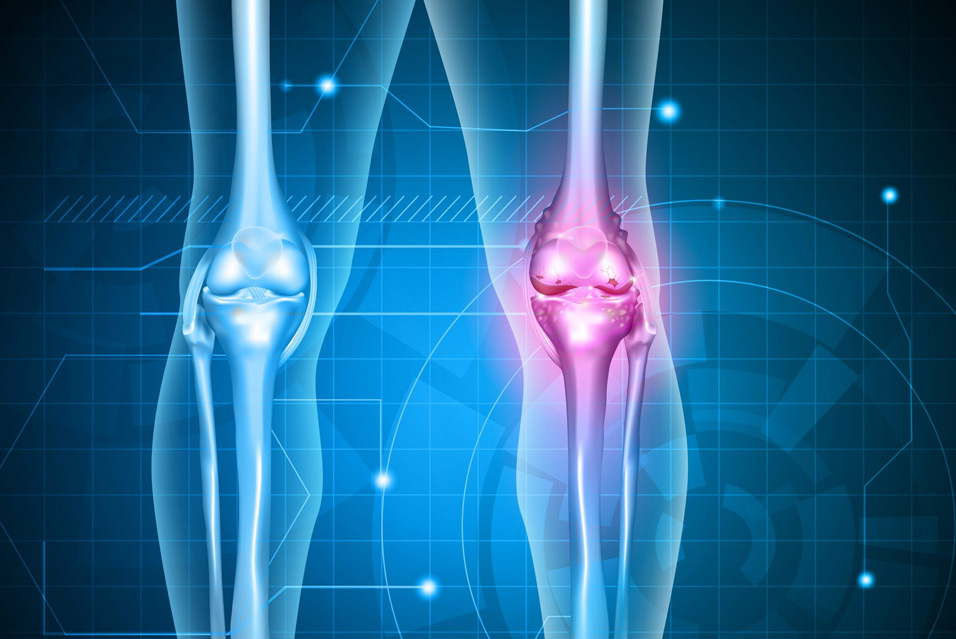

Хондросаркома – это злокачественная опухоль, которая развивается из клеток хрящевой ткани. Является вторым по распространенности видом первичного рака костей у взрослых. Чаще всего поражает кости таза, бедра, плеча, ребра и лопатки, но может возникать в любой части скелета или, реже, в мягких тканях. Характеризуется разнообразным клиническим поведением от медленно растущих, низкоагрессивных форм до быстро растущих и метастазирующих.

- Тупая, ноющая боль в области поражения

- Боль, которая может усиливаться ночью и не проходит в покое

- Постепенно увеличивающееся, плотное образование (опухоль или припухлость)

- Ограничение подвижности в суставе (если опухоль рядом)

- Патологические переломы (переломы при минимальной нагрузке из-за слабости кости)